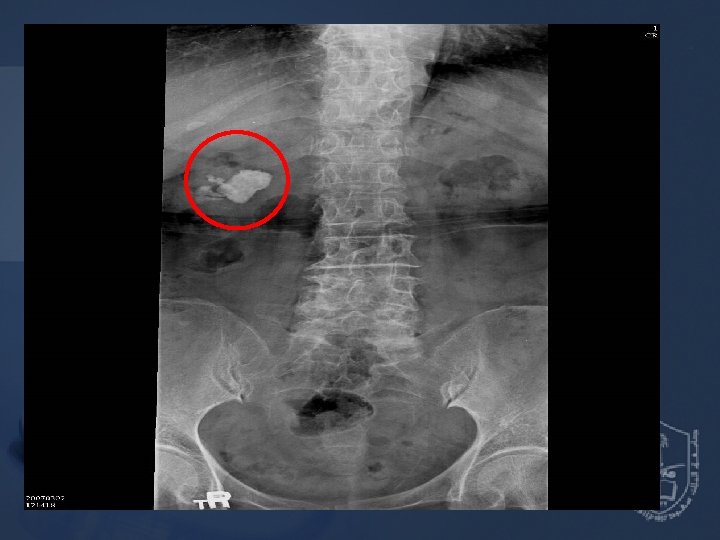

The Patient Past history : Hypertension under regular control Senile dementia (mild) Preoperative diagnosis : Right renal stone (3. 2 cm) Operation planned : Right PCNL (percutaneous nephrolithotomy)

Pre-anesthetic Assessment EKG : Normal sinus rhythm CXR : Borderline cardiomegaly & tortous aorta Lab data : Hb 10. 5 / Hct 33. 2 BUN 24 / Creatinine 1. 1 GOT 14 PT, a. PTT WNL

Preop